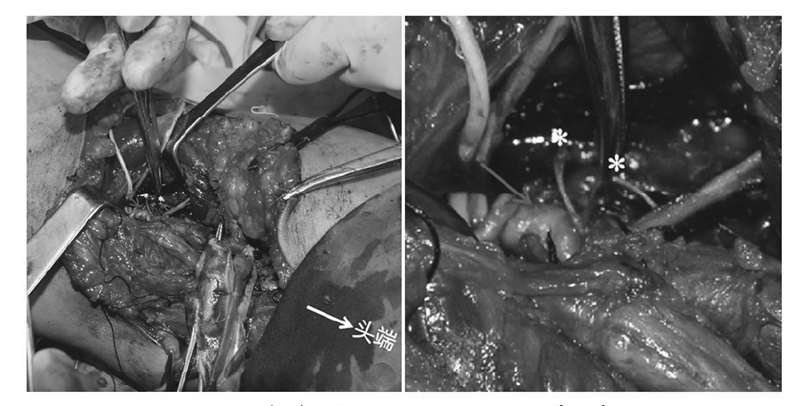

术后第1天复查下肢血管彩超及实验室检查凝血功能,发现腘动脉血栓形成及凝血功能异常(图4~5),患者未诉 不适。体检发现足背动脉搏动较对侧弱,皮温略低,末梢血氧饱和度90%。请显微外科及心血管内科会诊后,心血管内科建议切开取栓,将病情告知患者及家属后行急诊取栓术。术中可见腘动脉分叉近端约2cm大小的半月板缝合袢将腘动脉捆扎,但仍有血流通过(图6),切开血管,取出血栓,取出半月板缝合袢,松开止血带,见血流好,在显微镜下修复腘动脉,再次松开止血带,见动脉搏动良好,无漏血,足背动脉搏动好,末梢血氧饱和度99%,手术完毕。患者术后第1天开始主动活动,双侧皮温一致,未诉患肢疼痛,复查右下肢动静脉彩超示右侧动静脉血流通畅(图7),术后24个月随访患者右下肢活动功能良好,双下肢无明显肿胀,双侧皮温一致,小腿腿围基本一致,患者McMurray征阴性,前抽屉试验阴性,膝关节稳定性良好,活动度良好。

图6 术中照见 Omnispan(12°)系统(星号)将腘动脉捆扎(箭头)